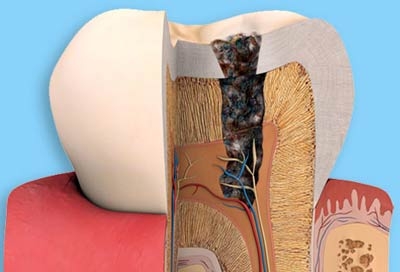

Điều trị nội nha

Mỗi năm trên thế giới hàng triêu chiếc răng đã được cứu sống nhờ điều trị nôi nha....

Phục hồi thân răng sau điều trị

Răng chúng ta phía ngoài là men, bên trong là ngà, trong cùng là vùng mô mềm gọi...